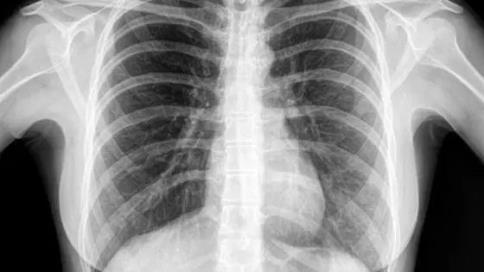

首先,這些網(wǎng)絡的潛在神經(jīng)表示非常復雜,需要使用大量的訓練樣本來完成模型訓練。但是截止到提交,這個新冠肺炎測試工具只看到了50個肺部圖像。

對于這樣一個超過150層,超過2000萬個參數(shù)的網(wǎng)絡來說,如此有限的訓練樣本集顯然是可笑的。

該模型通過肺部X射線圖像來學習。